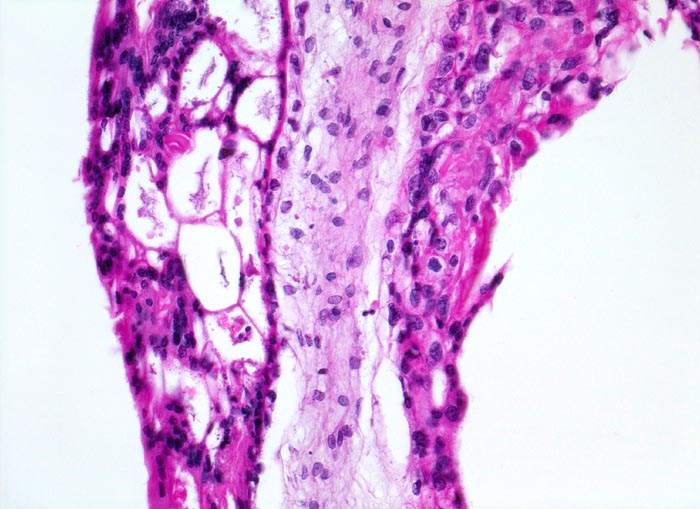

PathoPic ID 5127 - Blasenmole

Blasenmole

angeboren /genetisch/Missbildung

Abortmaterial

Paidopathologie

Ausgeprägte Proliferation von

Syncytio- und

Zytotrophoblastepithel.

beta HCG Level von 150'000 mIU/mL. Uterus zu gross für das Gestationsalter von 10 Wochen. Arterielle Hypertonie.

Histologie

200